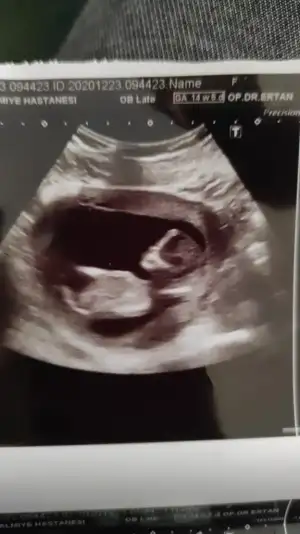

12+3 burda varmı bi tahmin

Hiç net değil USG piksel bozuk tip olarak tahmin edersem kız derimIkra meyra benden biktin biliyorum